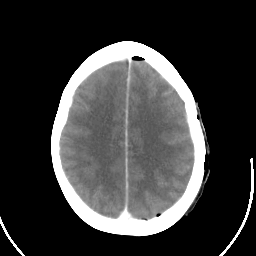

Metastatic bronchogenic carcinoma: Roentgen-ray CT (post-op) -- Slice #16

[Home][Help][Clinical] Slice 16